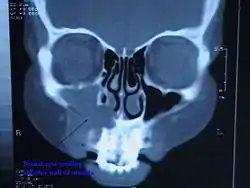

![]() مسح مقطعي محوسب خلال الرأس تظهر كيسا محيطا بالقمة على اليمين. مسح مقطعي محوسب خلال الرأس تظهر كيسا محيطا بالقمة على اليمين. | |